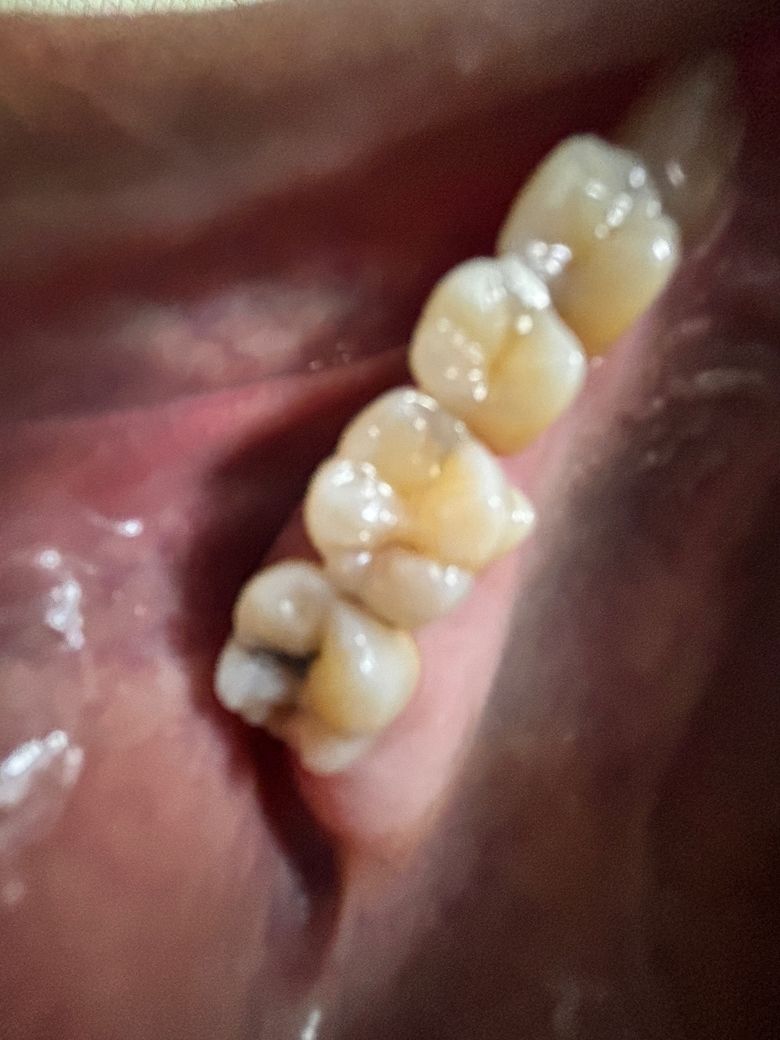

맨 뒤쪽 검은 부분은 치아 썩은 건가요??

사진이 흐릿한 점 감안하고 답변부탁드립니다

• 2번 째 사진

육안상으로는 충치가 상당히 깊어 보일것같습니다. 그리고 치아 사이에도 충치가 많아 보이니 엑스레이 촬영후에 치료를 하시는게 좋을것같습니다.

네 사진상 충치 있고 꽤 깊어 보이기도 합니다 신경치료 가능성 있습니다 치과 가능한 빨리 가보세요

시리거나 통증은 없는데 신경치료까지 해야할까요? -> 네 그럴 가능성이 높아 보입니다.

사진으로 봤을 때는 충치가 있는 것으로 보입니다. 충치가 있을 경우 해당 부위에 이물질이 남아 있게 되어 충치가 더 진행될 수 있으니 충치를 치료하는 것이 좋습니다.

자세한 확인을 위해서 치과에서 진료를 받아보는 것을 권유드립니다.